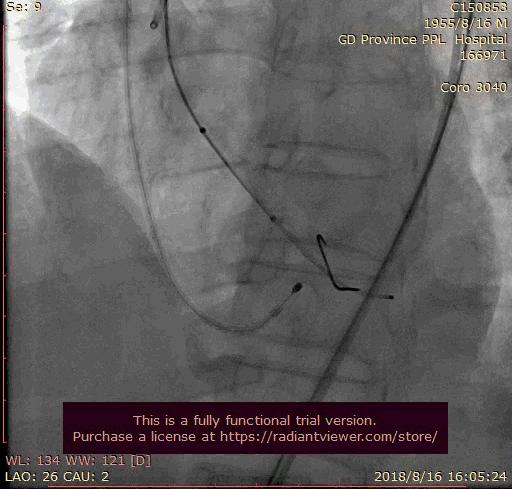

首枪造影

Numed20预扩

瓣膜释放前1/3

瓣膜位置调整